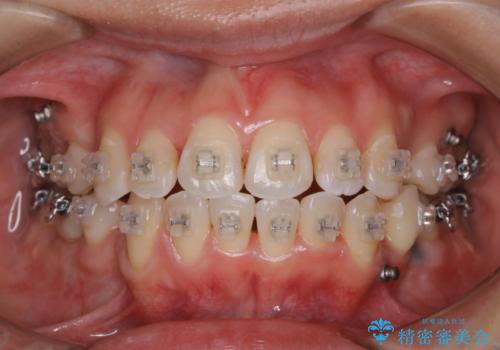

ワイヤー矯正中のクリーニング

ワイヤー矯正中の患者様で、歯石やプラーク、着色が多くついていました。

数ヶ月ぶりのクリーニングになり、ご自身でも余り丁寧に磨けていなかったそう。再度、歯ブラシの仕方について指導し頑張ってもらうよう説明しました。

汚れや着色がないだけでだいぶ見た目も、印象も変わっていくため、定期的にクリーニングを行うことをお勧めします。